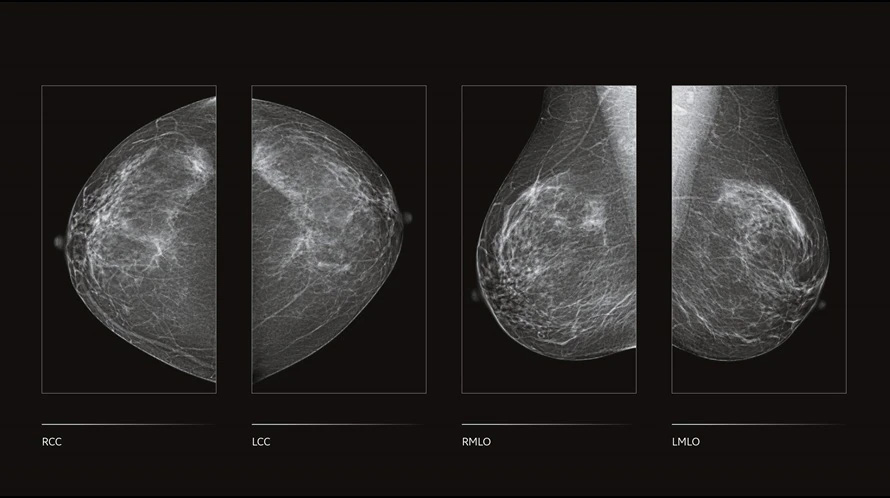

GE Senographe Crystal Nova — полноформатная цифровая маммографическая система, созданная для центров раннего выявления и специализированных отделений лучевой диагностики. Используется высокоэффективный детектор с повышенной детективной квантовой эффективностью, архитектура системы позаимствована у премиальных линеек GE, что обеспечивает стабильное качество визуализации при низкой дозовой нагрузке. Автоматическая оптимизация параметров экспозиции (AOP) подстраивает напряжение и ток рентгеновской трубки под плотность и толщину груди, а программная обработка eContrast улучшает локальный контраст без усложнения рабочего процесса.

- Полноформатная цифровая маммография на базе высокоэффективного плоскопанельного детектора из премиальной линейки GE.

- Алгоритм обработки eContrast для усиления локального контраста и повышения читаемости деталей паренхимы.